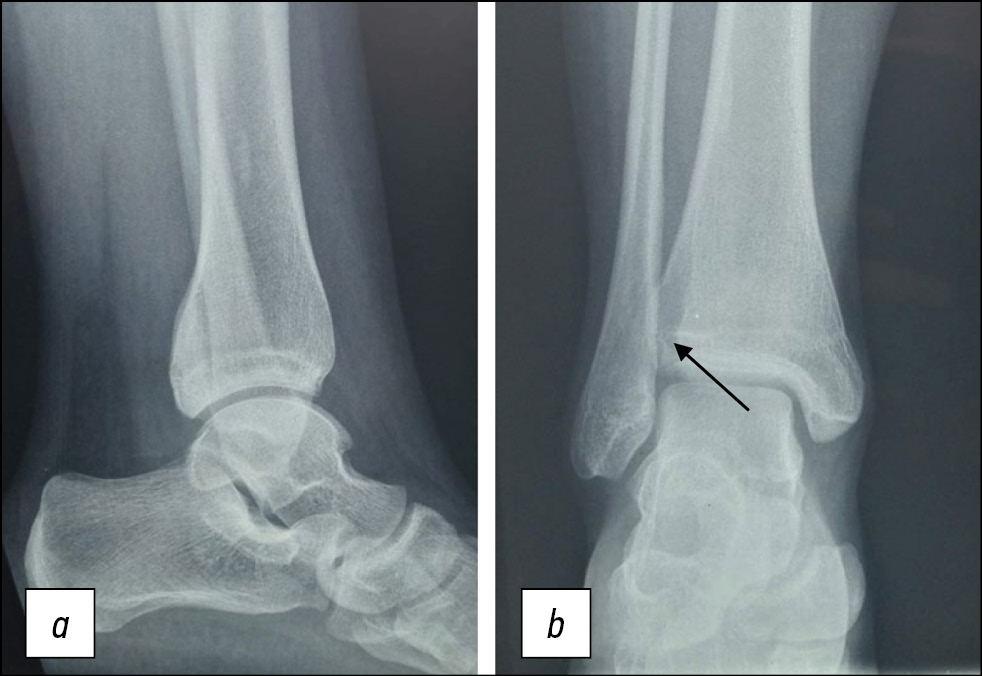

Пациентка А.А., 13 лет, диагноз: «Закрытый эпифизарный перелом переднего бугорка правой большеберцовой кости со смещением. Разрыв дистального межберцового синдесмоза». Ребёнок поступил в отделение спустя 3 нед с момента травмы с жалобами на боль при ходьбе и чувство нестабильности в правом голеностопном суставе. Травма получена в результате непрямого супинационно-инверсионного механизма. Первоначально пациентке поставлен диагноз: «Дисторсия связочного аппарата правого голеностопного сустава», рекомендована иммобилизация на 2 нед полужёстким ортезом. Клинически наблюдали пастозность в области правого голеностопного сустава, локальную болезненность при пальпации. Для определения повреждения межберцового синдесмоза использовали клинические тесты: тест сжатия и тест внутренней ротации стопы. Оба теста оказались положительными. Пациентке было выполнено рентгенологическое исследование в прямой и боковой проекции (рис. 1). Для уточнения наличия повреждения межберцового синдесмоза дополнительно сделаны рентгенологические снимки в синдесмозной проекции в сравнении со здоровым суставом под нагрузкой (рис. 2). В связи с тем, что клинически и рентгенологически обнаружили признаки повреждения межберцового синдесмоза, для уточнения характера повреждения использовали метод УЗ-диагностики. Обнаружены свободный костный фрагмент в проекции межберцового промежутка и наличие анэхогенных включений в области вплетения связки, что служит достоверным признаком разрыва. Поскольку были найдены достоверные признаки разрыва, и имелся выраженный болевой синдром, проба с наружной ротацией стопы не проводилась (рис. 3).

Рис. 1 (a, b). Рентгенограммы пациентки А.А. в прямой и боковой проекции. Перелом переднего бугорка правой большеберцовой кости со смещением.

Fig. 1 (a, b). X-rаy of the patient AA in frontal and lateral side. Epiphyseal fracture of the anterior tubercle of the right tibia with displacement.